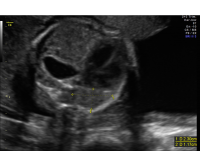

Congenital diaphragmatic hernia chest_view

A congenital diaphragmatic hernia (CDH) is caused by a defect in the diaphragm. The diaphragm is the muscle that separates the chest cavity from the abdominal cavity. CDH occurs in approximately one in 3,000 to 5,000 live births.